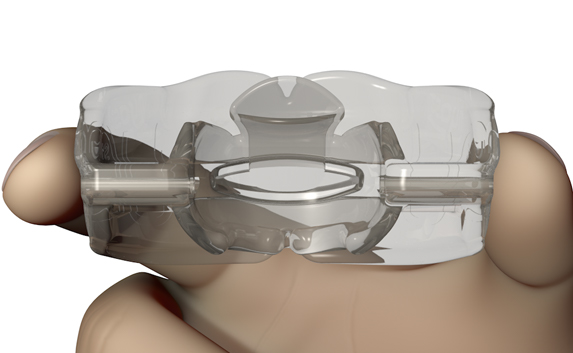

The Myosa® for TMJBDS® S1H is specifically designed for patients who are breathing and disordered sleep (BDS) primary with moderate to severe BDS as indicated by a Breath Hold Time (BHT) of 20 or less. These patients may or may not have TMJ disorders, but due to the severity of their BDS, they require immediate improvement of their airway. The features of the appliance not only work to open the airway, but also allow patients to undertake initial exercising of the lip, tongue and airway muscles. Progress to the S1 when the patient’s BHT reaches 20 seconds or more.